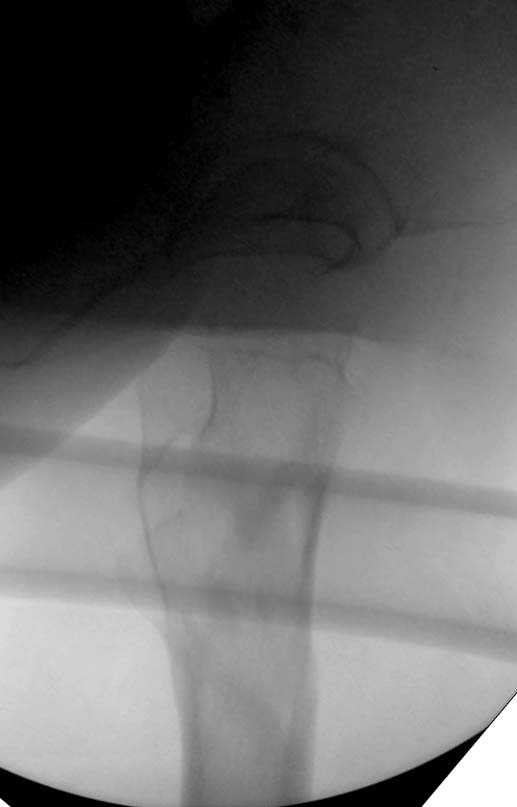

При первом послеоперационном поликлиническом осмотре больная предъявила жалобы на боли в бедре. В серийных снимках обнаружен продольный перелом верхнего отдела бедра.

Считаем, что техническая ошибка произошла во время установки гвоздя, когда рассверливанию канала не уделили должного внимания. Канал остался узковат, и гвоздь был забит с силой. Полная нагрузка конечности приостановлена на две недели, и боли в конечности изчезли. Больная начала нагрузку и перелом срастается.-- Djoldas Kuldjanov, M.D.Associate ProfessorDepartment of Orthopedic SurgerySt. Louis University

Мне думается, что варусное положение проксимального отломка на последующих снимках не более чем проекционный феномен. Раскол же диафиза вдоль, наверняка, связан с чрезмерно насильственным введением штифта. Вообще, при реверсивных, да и обычных вертельных переломах, многие давно отказались от короткой Гаммы в пользу long-версии. Но в любом случае надо быть на 100 уверенным в подготовке канала.